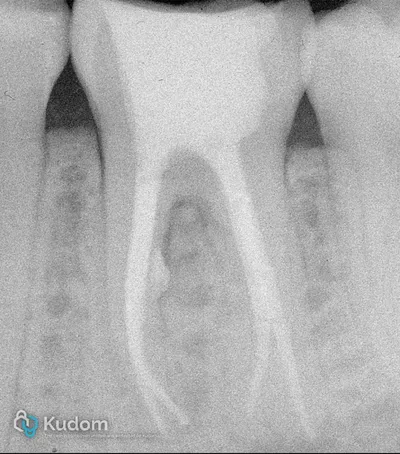

Trattamento endodontico di un primo molare mascellare, con attenzione alla corretta detersione, sagomatura e otturazione.